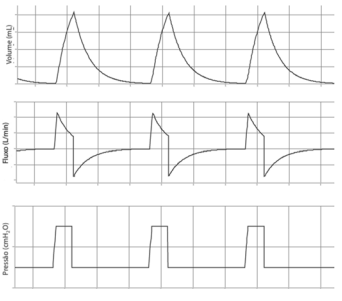

Um paciente foi admitido no pronto-socorro com quadro de covid-19, que evoluiu com a necessidade de intubação orotraqueal e sedação profunda. O gráfico abaixo representa o painel de seu ventilador mecânico. As curvas superior, média e inferior representam, respectivamente, volume, fluxo e pressão.

Com base nesse caso hipotético, assinale a alternativa que apresenta o modo ventilatório representado e seu parâmetro de ciclagem.